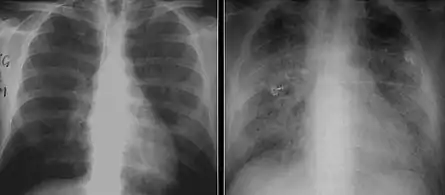

The diagnosis can be confirmed by the characteristic appearance of the chest X-ray and an arterial oxygen level (PaO2) that is strikingly lower than would be expected from symptoms. Gallium 67 scans are also useful in the diagnosis. They are abnormal in about 90% of cases and are often positive before the chest X-ray becomes abnormal. Chest X-ray typically shows widespread pulmonary infiltrates. CT scan may show pulmonary cysts (not to be confused with the cyst-forms of the pathogen).

Chest X-ray of increased opacification (whiteness) in the lower lungs.

These chest radiographs are of two patients. Both show ground glass opacities. The left X-ray shows a much more subtle ground-glass appearance while the right X-ray shows a much more gross ground-glass appearance mimicking pulmonary edema.[7]